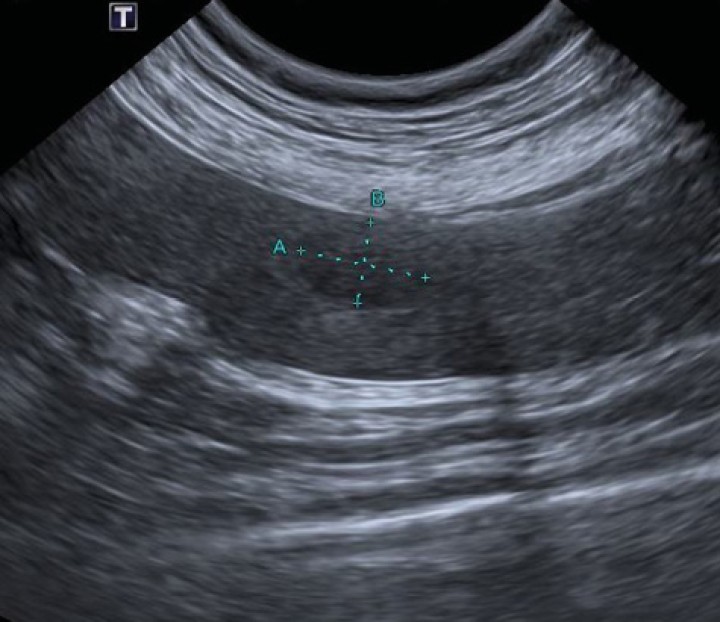

Por este motivo, se realizó una ecografía torácica (Fig. 3) como siguiente paso donde, mediante un abordaje paraesternal izquierdo, se identificó una masa heterogénea y principalmente hipoecoica, de grandes dimensiones (aprox. 8 x 6 cm) y bordes irregulares, ocupando el mediastino craneoventral y que, tras ser evaluada con Doppler color, resultó no presentar vascularización. Además, se observó una pequeña cantidad de derrame pleural anecoico. Sin embargo, no se identificaron linfadenopatías, por lo que no se pudo descartar un origen ganglionar de la misma. El corazón no mostró alteraciones.

<p>Ecografía torácica en la que se observa una masa heterogénea y principalmente hipoecoica en el mediastino craneal.</p>

Ecografía torácica en la que se observa una masa heterogénea y principalmente hipoecoica en el mediastino craneal.